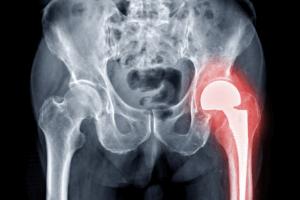

Κατ’ οίκον αποκατάσταση μετά από αρθροπλαστική ισχίου με τη μέθοδο Fast Track

Η αρθροπλαστική ισχίου fast track αποτελεί μια σύγχρονη χειρουργική προσέγγιση που εστιάζει στη μείωση του μετεγχειρητικού πόνου, στον περιορισμό των επιπλοκών και…

αποκατάσταση ηλικιωμένων μετά από κάταγμα ισχίου

Η αποκατάσταση ηλικιωμένων μετά από ένα κάταγμα ισχίου αποτελεί μια κρίσιμη και πολυδιάστατη διαδικασία. Όμως, είναι πολύ σημαντική, καθώς καθορίζει σε μεγάλο…